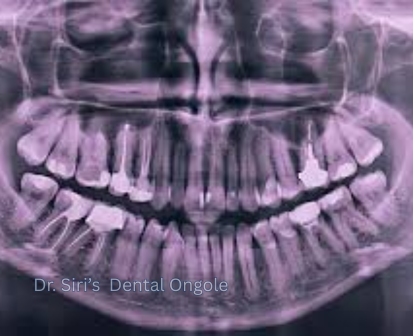

Dental X-Rays

Dental X-rays are an essential diagnostic tool that help dentists see what is not visible during a routine examination. They reveal hidden problems such as cavities between teeth, bone loss, infections, and impacted teeth, allowing for early and accurate treatment.

At Dr. Siri’s Dental, Ongole, we use safe and modern digital X-ray technology that minimizes radiation exposure while providing clear and detailed images for precise diagnosis and treatment planning.